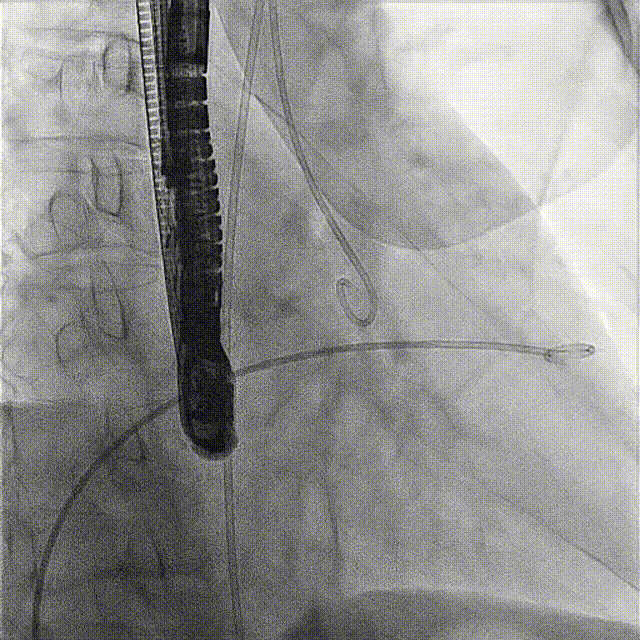

術(shù)前DSA

術(shù)前經(jīng)過(guò)全面系統(tǒng)的評(píng)估后,考慮患者存在高齡、心功能減低、三尖瓣瓣環(huán)重度擴(kuò)張(三尖瓣極重度反流)等高危因素,因此廈心結(jié)構(gòu)心團(tuán)隊(duì)聯(lián)合超聲心動(dòng)、麻醉及護(hù)理團(tuán)隊(duì),制定了詳盡的圍術(shù)期治療方案及術(shù)中治療難點(diǎn)預(yù)案。術(shù)中,由王焱院長(zhǎng)主刀,在蘇茂龍主任超聲心動(dòng)團(tuán)隊(duì)的輔助,上海市第一人民醫(yī)院陸方林主任的協(xié)助下,僅用時(shí)30分鐘,即順利完成了三尖瓣原位置換的手術(shù)。術(shù)中患者血流動(dòng)力學(xué)穩(wěn)定,術(shù)后即刻顯示LuX-Valve Plus瓣膜位置良好,固定穩(wěn)定,瓣膜功能正常,無(wú)瓣周漏。